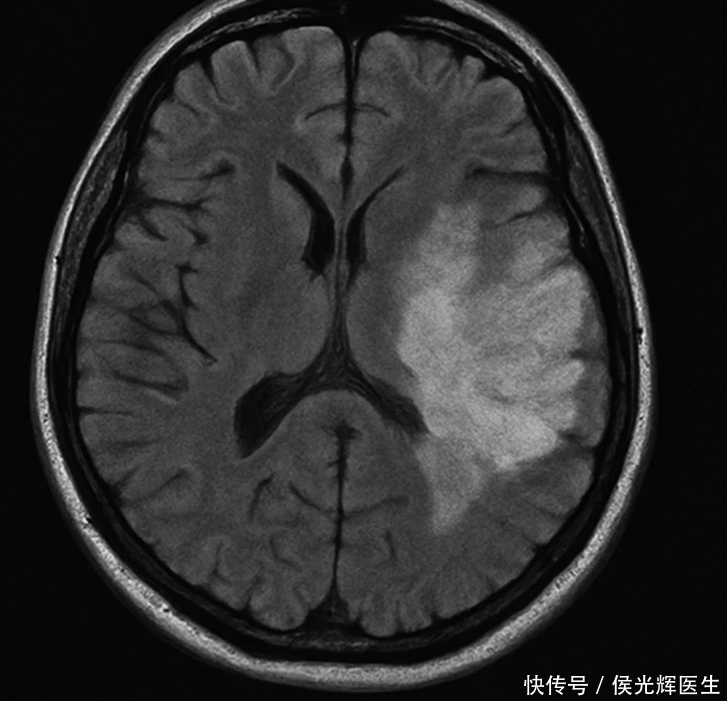

脑梗来之前,身体会“同时敲门”——①突发口齿不清、口角歪斜,别人听你像含着热粥;②一侧肢体突然无力、麻木,端杯、走路像“没插好电”;③视物模糊或双影,甚至一只眼一过性“黑一下”。

这三种若“突发、单侧、进行性”,尤其合并猛烈头痛、眩晕、呕吐或站立不稳,请立刻中断所有“讲道理”的自我安慰。判断口诀可以记“BE-FAST”:B平衡失调、E视力异常、F面部不对称、A手臂无力、S言语含混、T立刻就医。越快到医院,越有机会“把时间塞回去”。

一旦出现上述可疑信号,第一反应不是“等一会看看”,而是“立刻拨打急救电话”。不要自行驾车、不要揉按按摩、不要吞服来历不明的“活血药酒”。记下发作时间,便于医生评估溶栓/取栓窗口。到院后影像学判断缺血还是出血,治疗方向完全不同;而缺血性脑卒中的静脉溶栓、机械取栓,拼的就是分钟。把“体面”“不好意思”放在门外,把“时间就是脑细胞”扛在肩上——这才叫真正的冷静。